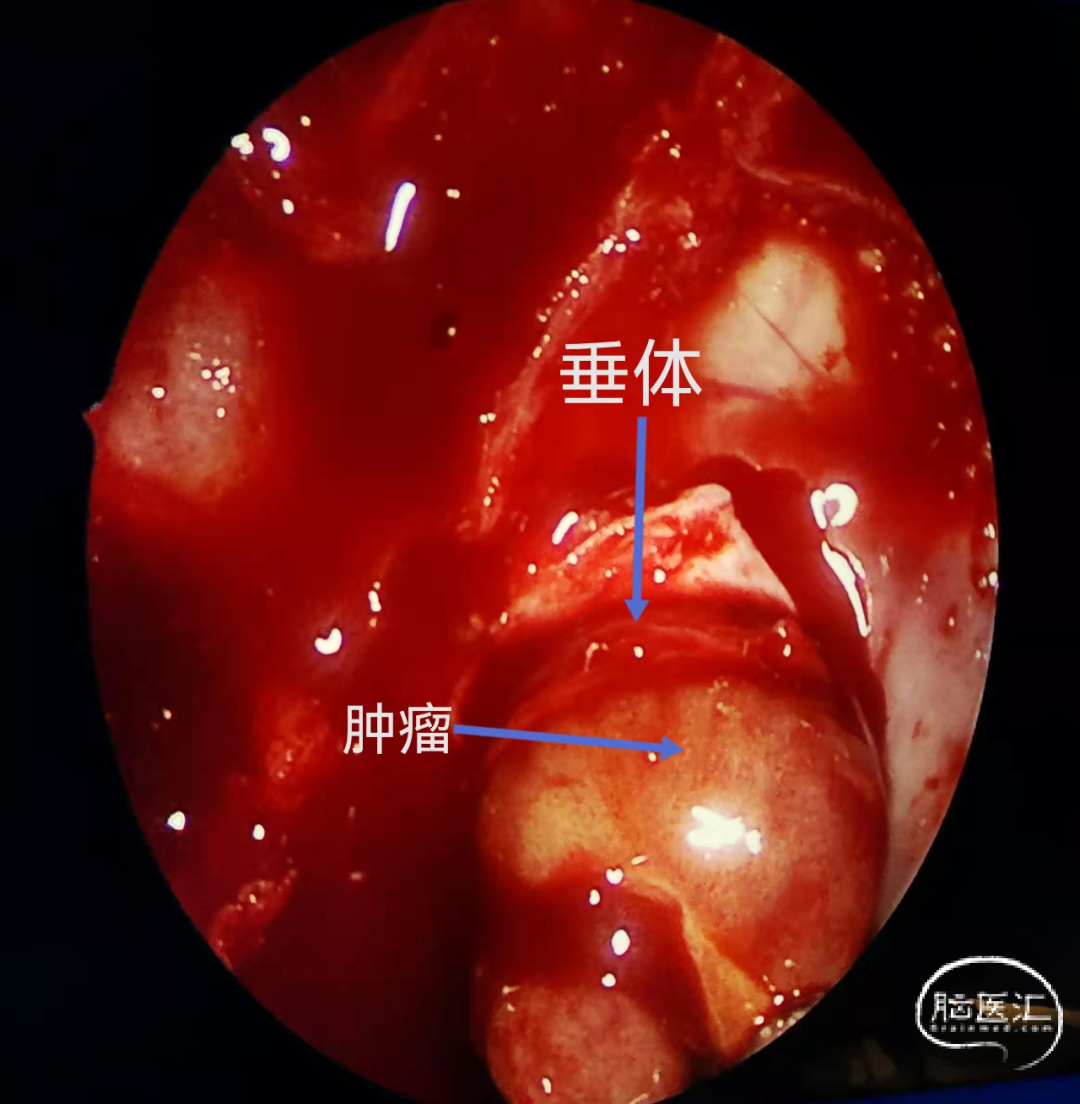

内镜下经鼻手术切除侵袭海绵窦的功能性垂体瘤

刘祺副教授神经内镜下的经鼻蝶垂体瘤切除术与脑室出血治疗

神经内镜经鼻蝶入路垂体瘤切除术 赞皇县医院外三科

内镜经鼻切除垂体瘤相关技术小结游学意大利十三